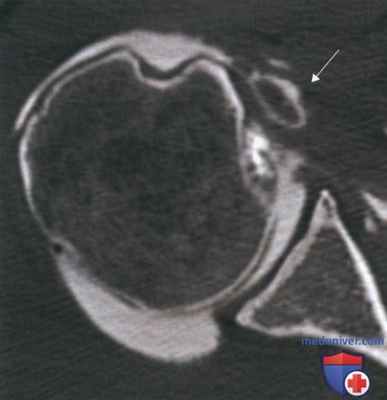

- Для выявления патологических изменений сухожилия двуглавой мышцы и ротаторной манжеты мы считаем весьма информативными исследования с контрастированием — КТ-артрографию и MP-артрографию. На рисунке 2 представлена КТ-артрограмма с признаками вывиха ДГБ (стрелка) в толщу подлопаточной мышцы